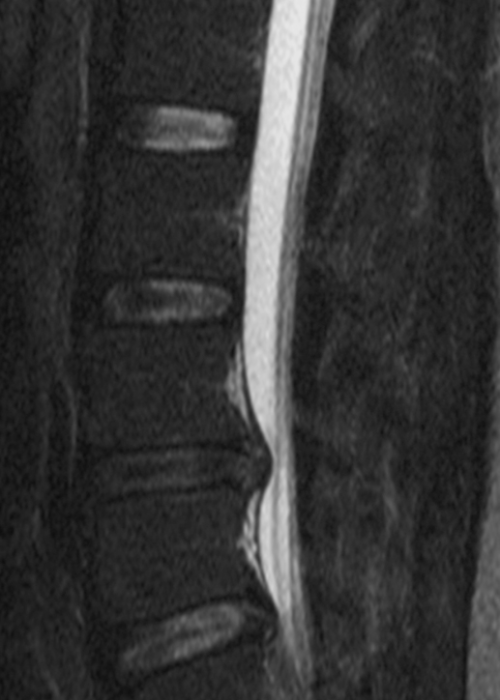

Herniated Disc

Herniated Disc

The spine is composed of over 2 dozen bones called vertebrae; in between, you have rubbery pads of cartilaginous material called discs. A herniated disc happens when one of those discs leaks material into nearby areas, pressing on nerves locally.

When the herniation is in your lower back, it’s your sciatic nerve that gets pressed.

While most disc herniations will resolve with time and physical therapy, there are instances when surgery is necessary to remove the disc material that’s causing sciatica.

Causes of a Herniated Disc

Unfortunately, there are countless reasons a disc in your lumbar area can herniate. While improper exercise form and direct trauma cause many cases; a herniation can occur as part of the aging process.

As we age, the material holding the jelly-like center of the disc becomes desiccated and more likely to crack, allowing this material to escape.

Herniated Disc

Herniated Disc